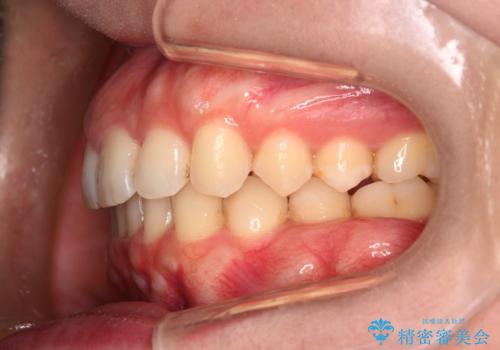

噛み合わせをよくするために、ワイヤー矯正とインビザライン矯正のどちらの期間も必要な箇所にゴム掛けを行いながら治療を行いました。

下の前歯のがたつき改善にはIPR(歯と歯の間を削る処置)を行いました。

ゴム掛けを頑張っていただいたので、噛みあわせも改善され綺麗な歯並びになりました。